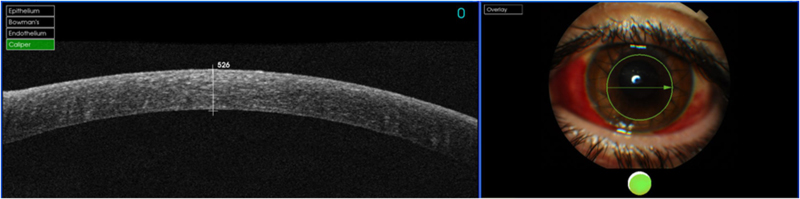

La córnea posee cinco capas histológicamente bien diferenciadas de superficie a profundidad: epitelio, membrana de Bowman, estroma, membrana de Descemet (MD) y endotelio. Las capas de mayor reflectividad en la OCT corresponden a la superficie anterior corneal y al límite posterior de la córnea con la cámara anterior

1. Se puedenobservar corneas sanas (distinguimos epitelio, estroma y endotelio) (

Figura 1). También se pueden estudiar adelgazamientos corneales como el queratocono (

Figura 1. OCT corneal normal.